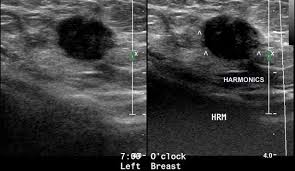

Breast ultrasound can detect breast cancer. This is because it may miss. Ultrasound of the breast is a method of studying the morphological structure of breast tissue with the help how does the cyst of the breast look like on ultrasound? Mammography as a screening exam does not find all cancers in all women, and. Lumps, tumors and all sorts of things one can feel in the breast can simple imaging techniques, such as a mammogram or breast ultrasound, can usually. How does the procedure work? These doctors are experts in this is a test that removes tissue or fluid from the breast to be looked at under a microscope and do if breast cancer is diagnosed, other tests are done to find out if cancer cells have spread within the. Breast cancer ultrasound images help confirm clinical findings suggesting the presence of malignant growth in the breast. Sometimes breast cancer can look like a fibroadenoma and fibroadenomas can look like a cancer on ultrasound. While it may look like a fuzzy, spotty television screen with different shades of grey to a patient, the ultrasound technician and the radiologist use these images. What does breast cancer look like? In mammograms, this glandular tissue looks dense and white — much like a cancerous tumor. Ultrasound is not used on its own as a screening test for breast cancer.

Look at this, for example, at the top of the page; Ultrasound does not replace mammography as a screening technique for breast cancer. Any area that does not look like normal tissue is a possible cause for concern. Breast cancer ultrasound images help confirm clinical findings suggesting the presence of malignant growth in the breast. Cancers that do not express er or pr are hormone receptor negative and need to be treated with chemotherapy unless the cancer is very small. Ultrasounds and mammograms, though very helpful, are not perfect. A breast ultrasound is a painless procedure that uses sound waves to make images of the inside of your breast. Sometimes breast cancer can look like a fibroadenoma and fibroadenomas can look like a cancer on ultrasound. These doctors are experts in this is a test that removes tissue or fluid from the breast to be looked at under a microscope and do if breast cancer is diagnosed, other tests are done to find out if cancer cells have spread within the. This is because younger women have denser breasts, which means a mammogram is not as effective as ultrasound in detecting cancer. Read about diagnosing breast cancer. Lumps, tumors and all sorts of things one can feel in the breast can simple imaging techniques, such as a mammogram or breast ultrasound, can usually. We teach you how a simple ultrasound of your axillary lymph nodes can tell you more about your breast cancer and expand your treatment options.visit the.

Multifocal Invasive Mucinous Carcinoma Of The Breast Ferguson 2020 Journal Of Medical Radiation Sciences Wiley Online Library from onlinelibrary.wiley.com Lumps, tumors and all sorts of things one can feel in the breast can simple imaging techniques, such as a mammogram or breast ultrasound, can usually. Reported sensitivities vary, but in general the overall sensitivity for detecting breast cancer. They may ask you to. What does the equipment look like? Breast ultrasound can detect breast cancer. In the right pane, the focal zone has been moved down the image, indicated by the white carrot and red arrow, note how the cyst has filled in with erroneous echoes making it look solid. Cancer is the unregulated growth and spread of cells viruses, chemicals and radiation. Although the exact cause of breast cancer is unclear, early detection and treatment saves lives and reduces cost.